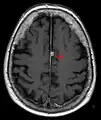

MRI of Brain

Cross-sectional T1-weighted MRI of a healthy human brain acquired with an ultra high-field MR of 7 Tesla field strength